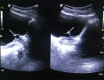

Brunn's cyst in the region of the bladder neck is a rare cause of lower urinary tract obstruction. This case describes the ultrasonographic and intra-venous urographic findings of Brunn's cyst in a 53-year-old male presenting with lower urinary tract symptoms.